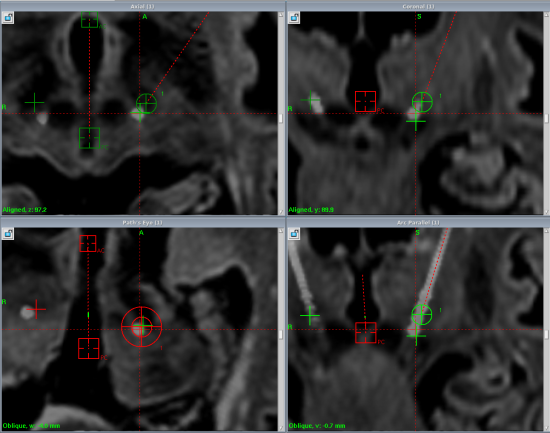

图示DBS电极精准植入双靶点Vim核团及PSA

手术在局部麻醉下进行。手术团队首先把DBS电极精准置入老人脑部双靶点;在孙大妈头脑保持清醒的前提下,术中临时外接刺激器,模拟术后疗效及可能产生的副反应。随着刺激参数的增大,她的右手逐步停止抖动,并且没有了麻木感,写字的线条也变得平稳流畅。术后一个月,当正式启动DBS时,老人的右手已经完全听从自己大脑的指挥,不再不受控制地摇来晃去;系纽扣、端水杯、用筷子夹菜等精细动作都一气呵成,说起话来也不再“跑调”了。现在,孙大妈已回归到老伙伴们的行列中。